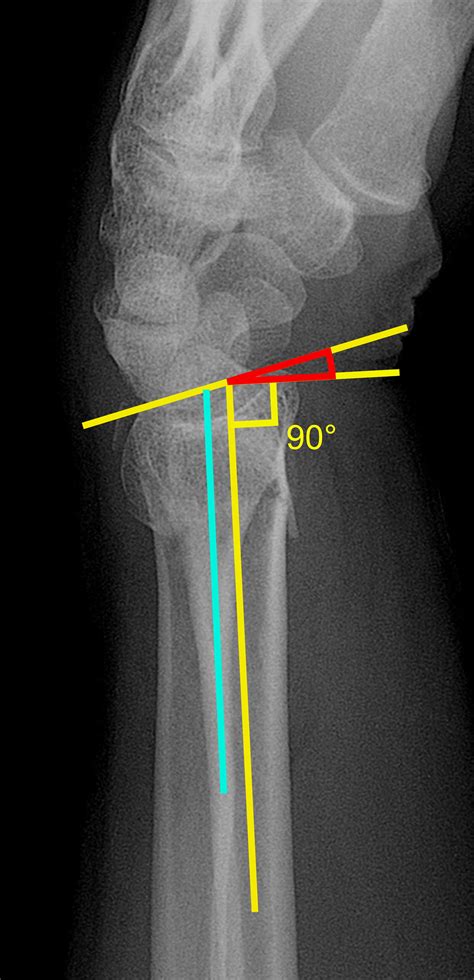

Radiographic Diagnosis of Scapholunate Dissociation Among ...

Radiographic Diagnosis of Scapholunate Dissociation Among ... from www.jhandsurg.org